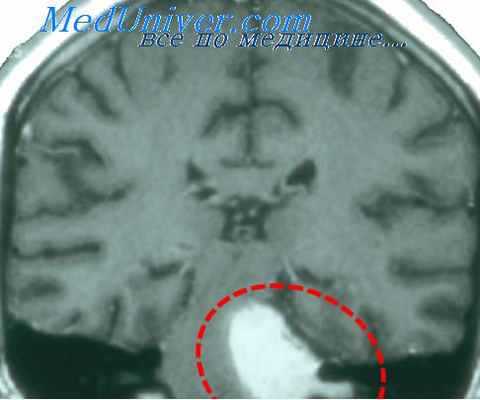

При изолированном поражении блуждающего нерва речь больного приобретает носовой оттенок, на стороне очага мягкое небо свисает, малоподвижно или неподвижно, язычок отклоняется в здоровую сторону. Небный рефлекс отсутствует (Рис. 65). Необходимо иметь в виду, что у больных с хроническим или острым тонзиллитом, курильщиков нередко отсутствуют небные рефлексы, язычок может отклоняться. При этом он обычно гиперемирован, припухший (увеличен в размерах).

При выключении функции отдельных веточек блуждающего нерва может развиться паралич гортани. В этом случае голосовая связка на стороне очага занимает срединное положение (Рис. 66), не сокращается при фонации и дыхании, голос становится хриплым. При процессах в области шеи может страдать верхний гортанный нерв. При этом кроме анестезии слизистой оболочки гортани нарушается функция т.